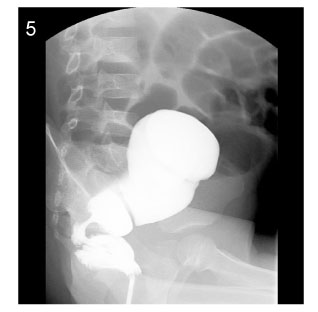

Fig. 5

Image of barium enema at the age of 5years (Case No. 6).

Fig. 5 Image of barium enema at the age of 5years (Case No. 6).